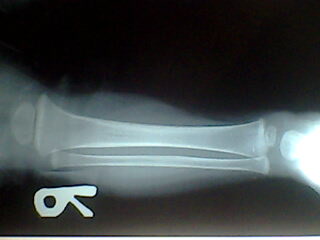

标题: PED0257:小腿

小孩腿痛波形

腓骨骨质溶解,大块骨质溶解症可能性大,建议进一步询问病史,进一步检查。有既往片价值更高。

左腓骨呈容骨性破坏。骨皮质及骨髓腔均破坏,下段骨不连续,周围软组织肿胀。考虑骨尤文氏肉瘤可能性大。

尤文肉瘤的明显软组织肿块与较小骨质破坏不成比例,本例似乎不符合。应考虑腓骨骨质溶解,建议询问家族史。